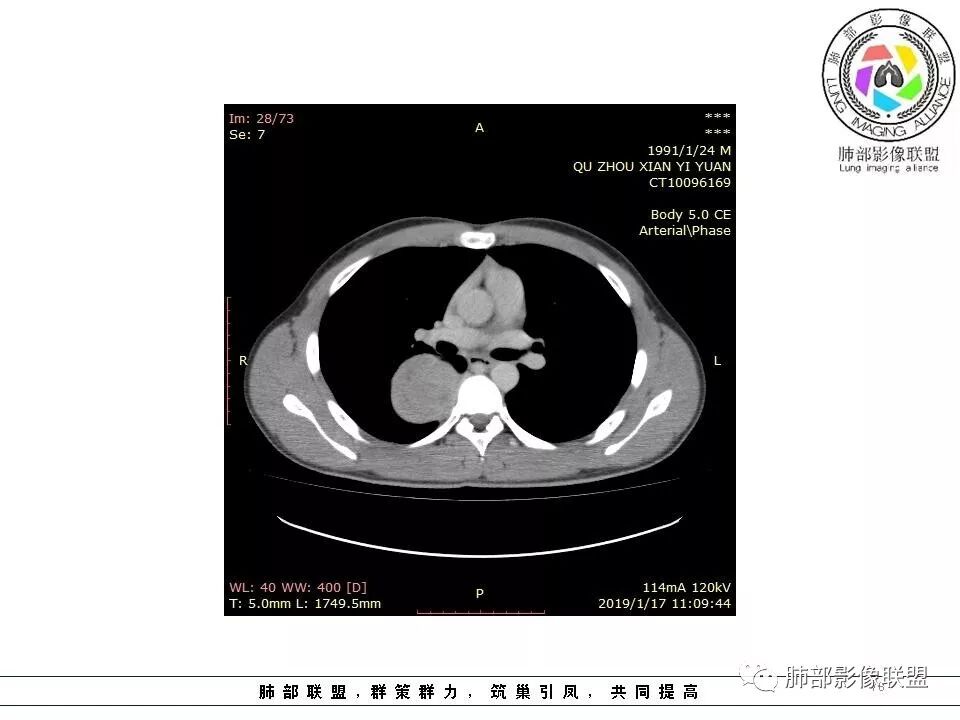

右后纵膈脊柱旁软组织占位,形态规则类圆,边缘光整,肺组织受压,胸膜尾,肋间动脉供血。中度不均匀延迟强化。

右后纵膈脊柱旁软组织占位,边界清晰,光整,肺组织受压。胸膜被掀起,肋间动脉供血,中度不均匀延迟强化。考虑神经鞘瘤,不除外纤维瘤

右后纵膈脊柱旁软组织影,与纵隔结构分界不清,形态规则类圆,边缘光整,肺组织受压,胸膜尾,肋间动脉供血。肺动脉推移,中度不均匀延迟强化。考虑神经来源,神经鞘瘤,神经纤维瘤二者不易鉴别。

青年男性,间断胸痛;右侧脊柱旁可见一类圆形软组织密度影,密度欠均匀,增强扫描呈轻中度持续强化,邻近肺组织及肺动脉推移,可见肋间动脉供血,部分胸膜下脂肪可见,部分层面似见与右侧椎间孔相连。考虑后纵隔神经源性肿瘤。

青年男性,间断胸痛。右后纵膈脊柱旁软组织占位,形态规则类圆,边缘光整,肺组织受压,D字征,胸膜尾,肋间动脉供血。中度不均匀延迟强化。无支气管进入考虑来源于肺外、肿块与脊柱间未见明显脂肪间隙,考虑来源于胸膜外,考虑神经源性肿瘤,建议穿刺活检。

1.右上胸内脊柱旁类圆形肿块,质地似乎比较坚实,密度稍显不均,但未显示明确的坏死。

如此密度形态的病灶位于肺边缘首先应当想到孤立性纤维瘤,可相邻胸膜未见明显的异常强化和胸膜方向延伸。

2.肋间动脉病供血也提示肿块来自后纵隔?

3.相邻椎间孔未见扩大,也未见块影延入椎管,易起自于神经根的鞘瘤似乎找不到支持点。

可惜未提供矢状位骨窗图像,如在肋骨内下缘观察到压迹有助于肋间神经的鞘瘤的判断,这是因为二者之间密切的毗邻关系。

4.静脉期轻度不均匀强化,注意不是环形强化,亦未见明确的“AB区”,这点也不支持神经鞘瘤。临床及病灶轻度强化都不支持副节瘤。